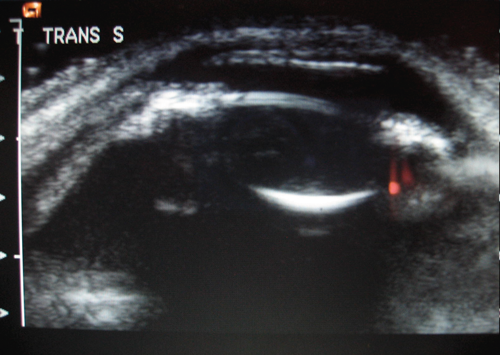

Anterior segment ultrasound biomicroscopy (AS-UBM) revealed anterior displacement of the iris-lens diaphragm and a shallow (1.6mm) nasal and temporal choroidal effusion (Figure 4).

Figure 4: AS-UBM of the right eye.